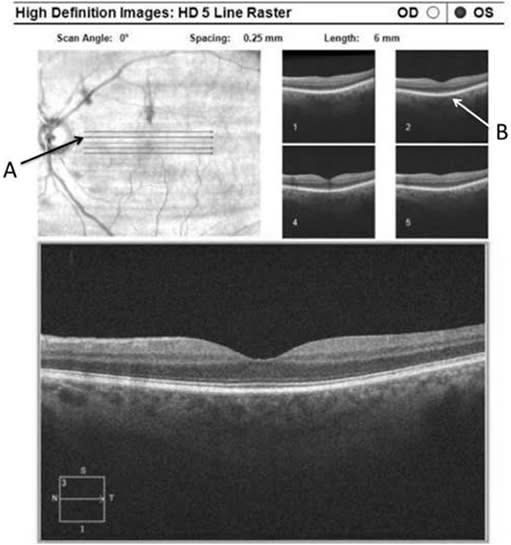

Qualitative analysis of the effects of LFT have been achieved with spectral domain OCT (SD-OCT) and scanning laser ophthalmoscopy by comparing shadows on the retina created by floaters before and after treatment. A recent study published in OSLI Retina in October 2018 on novel OCT applications, including shadow changes on a 5-line raster scan following vitreolysis, described cases in which patients had complained of a scotoma that would not go away.6 Multiple initial tests from other doctors did not reveal an etiology.

After further examination of the vitreous and evidence on SD-OCT of the shadow being cast by a large floater over the macula, YAG vitreolysis was performed. Following treatment, patients described resolution of the floater and the SD-OCT scans revealed resolution of the shadow that was cast on the retina (Figures 11 and 12).